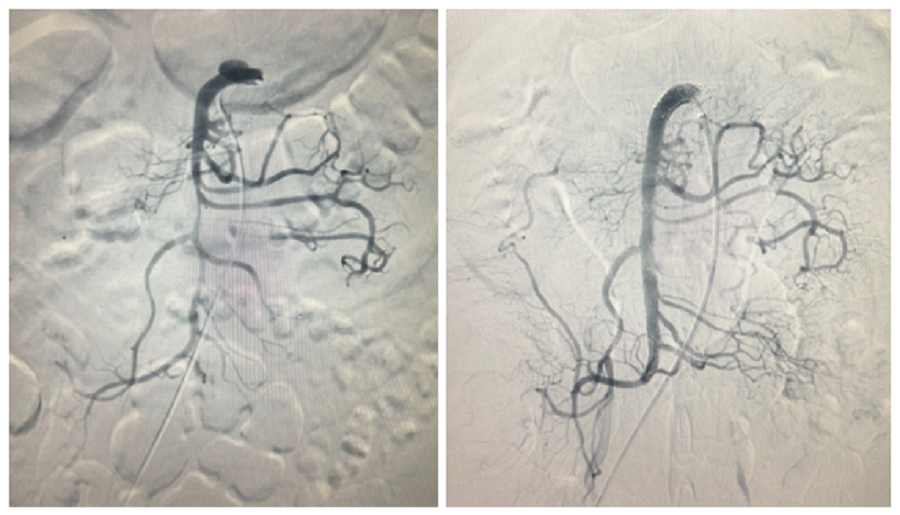

| Hệ thống động mạch treo tràng trên của người bệnh trước và sau khi can thiệp |

Tình trạng này khiến người bệnh bị thiếu máu ruột nghiêm trọng, diễn tiến hoại tử ruột non nếu không được xử lý kịp thời. Sau khi tiếp nhận bệnh nhân, bệnh viện đã hội chẩn chuyên khoa tìm giải pháp cứu chữa. Sau hội chẩn, các bác sĩ đã chỉ định can thiệp đặt stent vào vị trí bóc tách để tái thông hoàn toàn động mạch mạc treo tràng trên, ngăn chặn nhanh chóng diễn tiến thiếu máu và hoại tử ruột cho người bệnh.

BS Lê Anh Huy chia sẻ: “Sau khi can thiệp đặt stent, anh L. được các bác sĩ khoa Ngoại tiêu hóa và Hồi sức tim mạch theo dõi để tiến hành cắt đoạn ruột hoại tử kịp thời nếu can thiệp nội mạch không thể đạt hiệu quả tối ưu. Tuy nhiên, dưới hướng dẫn của hệ thống chụp mạch số hóa xóa nền (DSA), các bác sĩ đã đặt stent thành công một đoạn động mạch bị bóc tách dài hơn 100mm, giúp cải thiện đáng kể lưu thông máu đến ruột".